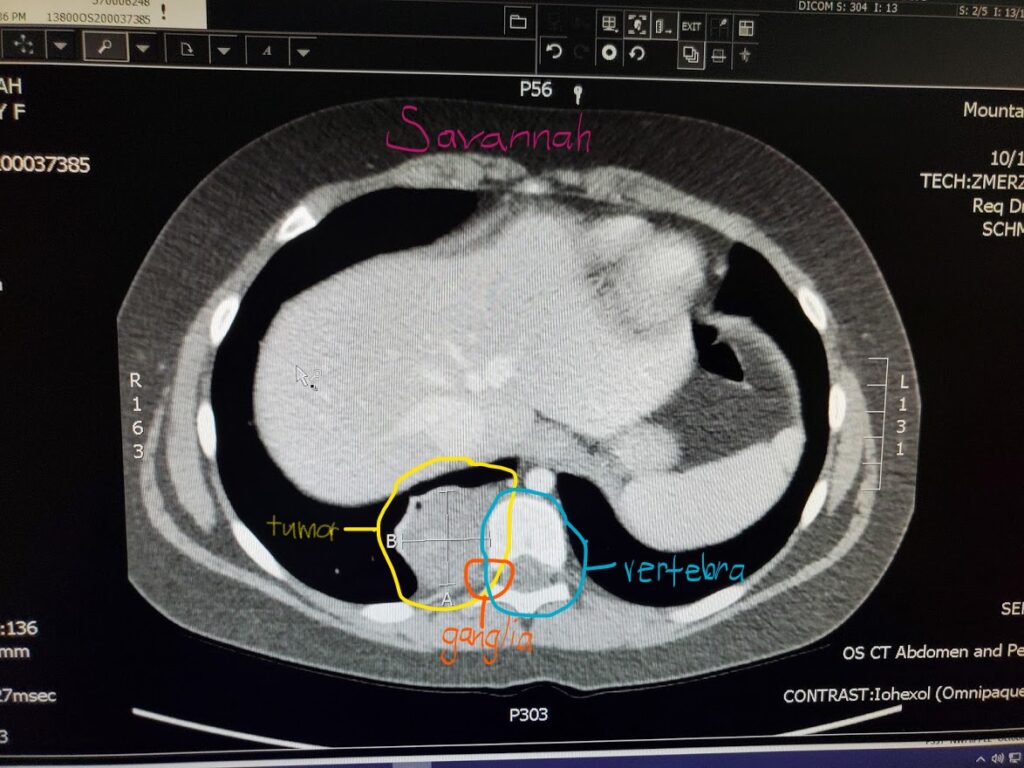

- The images below help you visualize where in Savannah’s body this tumor grew. The cells grew and multiplied into a mass that grew into her abdominal and thoracic cavity pushing against her right kidney, adrenals and diaphragm. Once it had grown that direction it started to push it’s way into the vertebra. It did NOT originate from the spine itself, but from the ganglia outside of the vertebra.